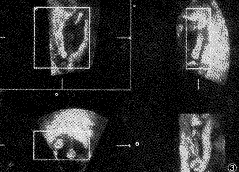

三维超声在显示脐带、四肢、胎儿外生殖器等方面也较二维图像更直观形象(图3),可帮 助操作者更全面了解上述结构。

图3 孕20周胎儿下肢二维及三维图像。右下角为三维图像